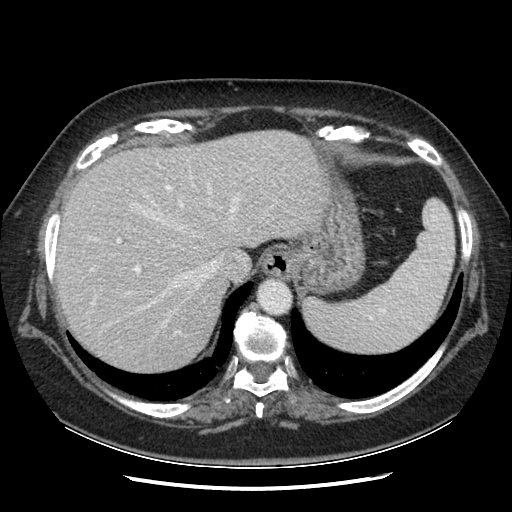

Original NATIVE CT scan (input)

Full window (WL 1023.5, WW 4095 β†’ Low βˆ’1024, High +3071)

Actual HU range: [-1024.0, 1077.0]

Original VENOUS CT scan

Actual HU range: [-1024.0, 1086.0]

Generated VENOUS CT scan (A→B translation)

Actual HU range: [-1024.0, 981.6]